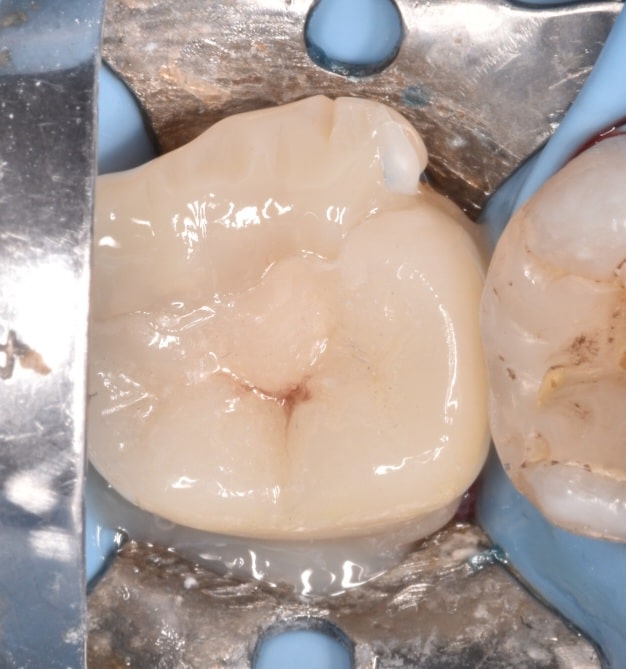

After removing the old filling and complete cavity design

IDS with gold standard cleafil SE bond

RC with flowable composite , Ever x posterior coverd by Tukoyama composite